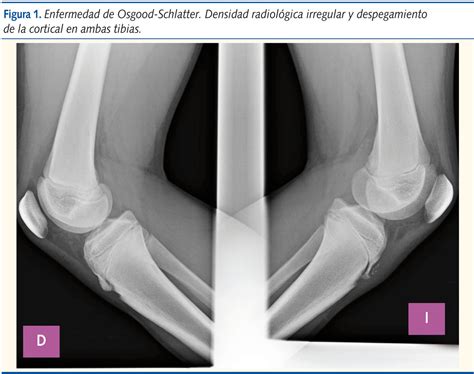

Diagnosing Osgood-Schlatter disease typically involves a physical examination and a review of the patient's medical history. The healthcare provider will ask about the symptoms, the onset of pain, and any recent changes in physical activity. They will also perform a physical examination to assess the affected knee, checking for tenderness, swelling, and any visible bumps.

In some cases, imaging tests such as X-rays, ultrasound, or MRI may be ordered to rule out other conditions and confirm the diagnosis. These tests can help visualize the tibial tuberosity and the patellar tendon, providing a clearer picture of the inflammation and any underlying issues.